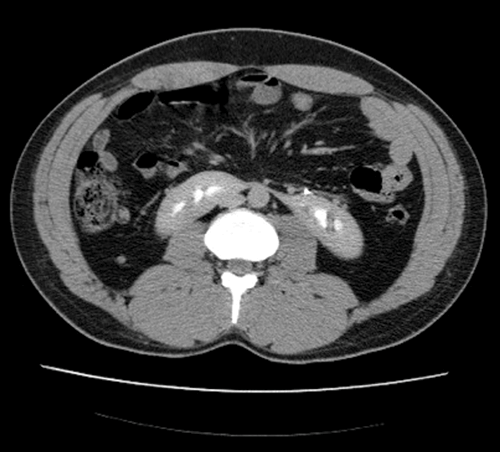

CT urogram demonstrates contrast in both collecting systems and fused kidney inferiorly, consistent with a horseshoe kidney; one case in 400.

Fusion of the metanephric masses, usually at the lower pole. Inferior mesenteric artery obstructs ascent of the isthmus, leaving the isthmus at level of L3/4.

Pelviureteric junction (PUJ) obstruction (approximately 33%), stones (20%), undescended testes, hypospadias and Turner’s syndrome.